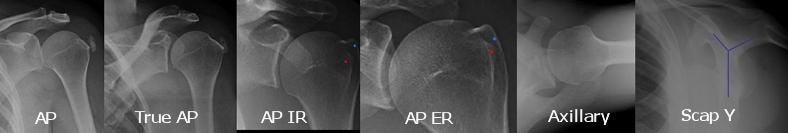

trauma 시에 가장 기본적인 검사는 AP와 axillary lateral view 입니다.

1. shoulder AP

glenohumeral joint space, DJD

Hill Sachs 를 확인하기 위해 ER/IR 해볼 수 있습니다..

2. True shoulder AP

Glenohumeral joint space, DJD, and proximal migration of humerus

glenoid에 수직으로 찍게됩니다. anatomical 한 AP 라고 할 수 있겠습니다.

3. axillary lateral view

상완골의 탈구/아탈구 를 확인해 볼 수 있습니다.

4. Scapular Y lateral view